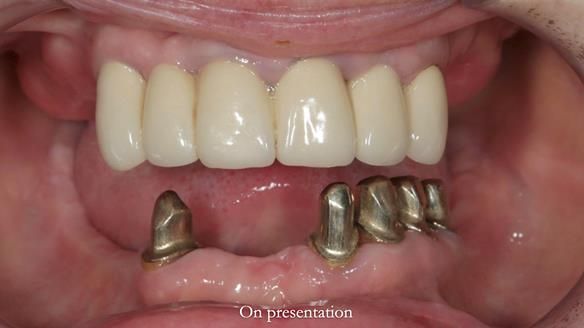

Replacement lower overdenture & upper RPD for Jackie

This Newsletter show Jackie’s case from start to finish – a technically demanding case involving replacing a telescopic crown-supported lower overdenture and an upper precision attachment-retained partial denture.

The real challenge was the lack of space for the lower overdenture.